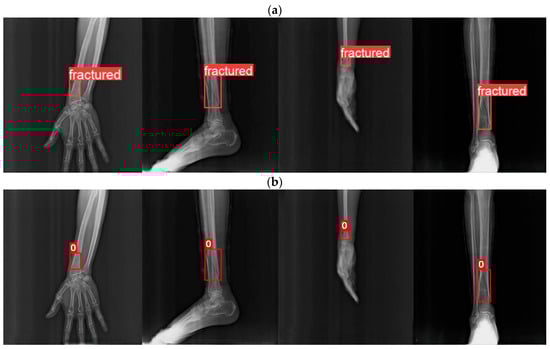

| Model | Precision (mAP 50) | Recall | F1 | Time (Seconds) |

|---|---|---|---|---|

| Yolov8m (Arm) | 0.594 | 0.491 | 0.538 | 6791 |

| YOLOv8m-HA(Arm) | 0.713 | 0.642 | 0.676 | 5931 |

| YOLOv8m (Arm and Leg) | 0.476 | 0.418 | 0.445 | 1763 |

| YOLOv8m-HA (Arm and Leg) | 0.592 | 0.473 | 0.526 | 1698 |